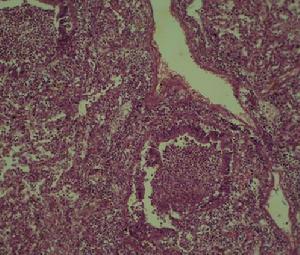

急性侵襲型肺麴黴病血常規:嗜酸性細胞升高。IgG沉澱素90%以上陽性。血清總IgE明顯升高。胸部X線表現為不同形態的肺浸潤,以支氣管肺炎最常見。多發性局灶性浸潤常分布在周圍肺野。部分病例表現類似肺栓塞或梗死。大葉肺實變和粟粒狀病變亦有所見。隨著病變進展,常常出現肺空洞,其中亦可形成急性麴黴球。並發胸腔積液時則見相應X線徵象。